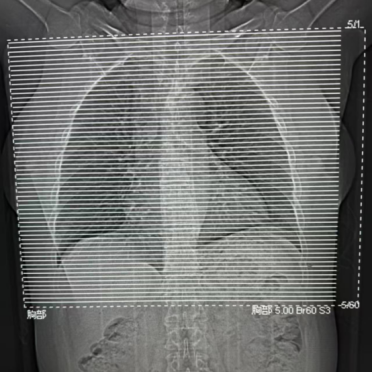

上图中虚线为定位线范围